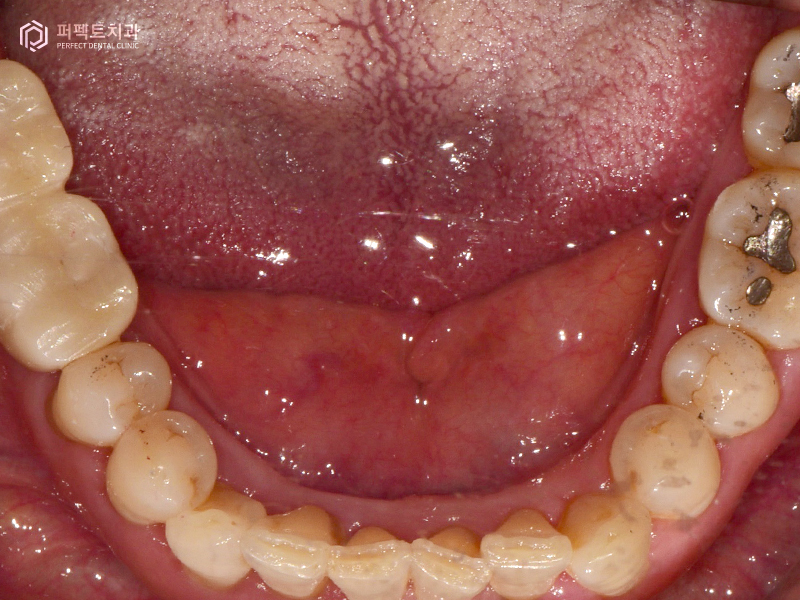

안녕하세요. 오늘은 여러개의 임플란트를 수복한 케이스에 대해 알아보도록 하겠습니다.

첫 내원 당시 엑스레이 사진을 보시면 알 수 있듯이 뼈가 많이 녹은 모습을 확인 할 수 있습니다. 실제로 오른쪽 아래 두개 치아는 흔들리고 있는 상황이었고, 위 어금니 치아도 괜찮아보일지 모르겠지만 많이 흔들리고 빠지기 직전의 상황이었습니다.

그리고 왼쪽에도 문제가 있는 치아가 있는데 이 곳은 어금니 두개가 없고 앞에 작은 어금니 두개를 이용해서 달려있는 치아를 하나 만들어 오랫동안 사용하고 있는 상황이었습니다. 결국 치아 두개가 없는 경우이기 때문에 앞에 치아가 무리하게 힘을 받아 앞에 있는 치아까지 망가진 경우라고 생각하시면 됩니다.

치료 계획은 오른쪽 아래 어금니 임플란트 2개, 흔들리는 위 어금니를 발치하고 1개, 왼쪽은 원래 없던 치아 2개와 옆에 흔들리는 치아까지 총 3개 의 임플란트를 식립하기로 하였습니다.

옆에 있는 치아는 붙어있는 크라운이기 때문에 제거 후 지르코니아 크라운으로 다시 수복하는 계획을 세웠습니다(총 임플란트 6개, 크라운 1개).

3번의 내원으로 임플란트 식립을 모두 마치게 되었고, 5~6개월이 지나고 임플란트와 뼈가 다 붙은 후에 다시 내원해주셨습니다. 본원에서는 구강을 스캔하여 3d로 만드는 작업을 하고 있는데, 이 작업을 통해 당일에 보철 6개를 끼워 마무리 하였습니다.

환자분의 경우 총 임플란트 6개, 지르코니아 크라운 1개의 치료를 받으셨는데 총 5번의 내원으로 해결을 할 수 있었습니다.